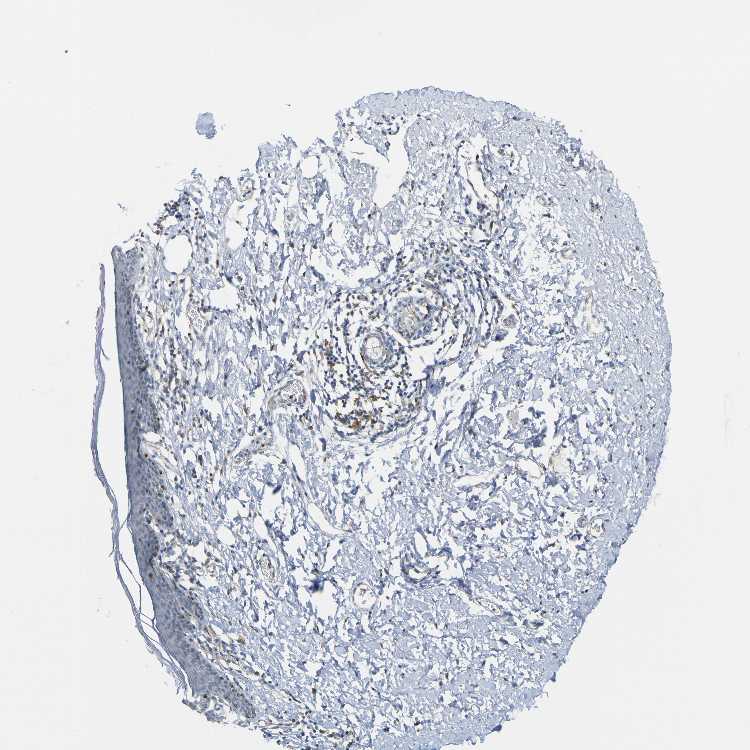

SKIN 1 - Antibody stainingi

Antibody staining in the annotated cell types in the current human tissue is reported as not detected, low, medium, or high, based on conventional immunohistochemistry profiling in selected tissues. This score is based on the combination of the staining intensity and fraction of stained cells.

Each image is clickable and will lead to virtual microscopy that enables deeper exploration of all samples and also displays staining intensity scores, fraction scores and subcellular localization as well as patient and tissue information for each sample.

Antibody HPA011332Antibody CAB009661

Langerhans Not detectedLow

Fibroblasts LowLow

Keratinocytes LowNot detected

Melanocytes MediumLow

SKIN 2 - Antibody stainingi

Epidermal cells LowNot detected